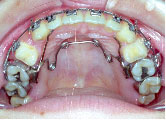

クォードヘリックスで上顎歯列を左右へ拡げた後、右上第1小臼歯を抜歯し、エッジワイズブラケットを付けて術前矯正を始めました。

術前矯正が終わりました。一見きれいになったようですが下あごはまだ左にずれたままです。

手術を担当する口腔外科医と最終打ち合わせをします。

手術時には必ずレントゲン上での計画(ペーパーサージェリー)と模型上でより具体的な計画を立てます。(モデルサージェリー)

上あごは左へ2mm,前方へ2mm(Le Fort 1型)、下あごは右後方へ3.5mm,正面右へ3mm、左後方へ2.5mm(IVRO)、また顔のバランスをとるためあごの先を前方に5mm移動しました。(genioplasty)手術が終わり、退院当日にできるだけ来院していただきます。この方は手術後13日目でした。

手術前に製作して渡しておいた装置(オルソサージカルスプリント)を入れ、ゴムをかけた状態できていただきます。